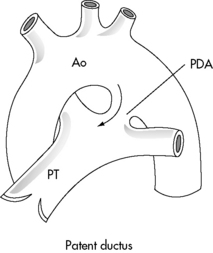

A patent ductus arteriosus (PDA) is persistence of the fetal structure, the ductus arteriosus, after birth (Fig. 8-30). The ductus arteriosus is derived from the left sixth embryologic aortic arch and connects the main pulmonary trunk (at the origin of the left pulmonary artery) to the descending aorta just below the left subclavian artery. When a right aortic arch is present, the ductus typically connects the right pulmonary artery with the right aortic arch. The ductus varies in length and is as large as or larger in diameter than the descending aorta in the fetus.449,628

image

Fig. 8-30 Patent ductus arteriosus (PDA). The PDA extends from the bifurcation of the pulmonary trunk (PT) to the aorta (Ao), joining the aorta just beyond the origin of the left subclavian artery.

(From Perloff M: Clinical recognition of congenital heart disease, ed 5, Philadelphia, 2003, Saunders. Fig. 20-1.)